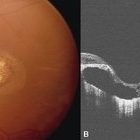

Fundus photo of a 43-year-old female with gradual onset diminution of vision in both eyes since 2-3 years. BCVA in OU was 3/60. She was diagnosed to have central areolar choroidal dystrophy(CACD). Central areolar choroidal dystrophy (CACD) is a rare inherited disease, which causes progressive profound loss of vision in patients during their fourth decade. It is characterized by atrophy of retinal pigment epithelium, photoreceptors and choriocapillaris. IT is a progressive macular dystrophy characterized by subtle, mottled depigmentation in the posterior pole in the early stages. The depigmentation area gradually enlarges until an oval or round surface of atrophy of the retinal pigmentary epithelium and choriocapillaris is formed. Drusen or flecks are absent in a typical presentation.

Photographer: Mr Ganesh Naidu

Imaging device: TOPCON DRI Triton

Condition/keywords: central areolar choroidal dystrophy (CACD)